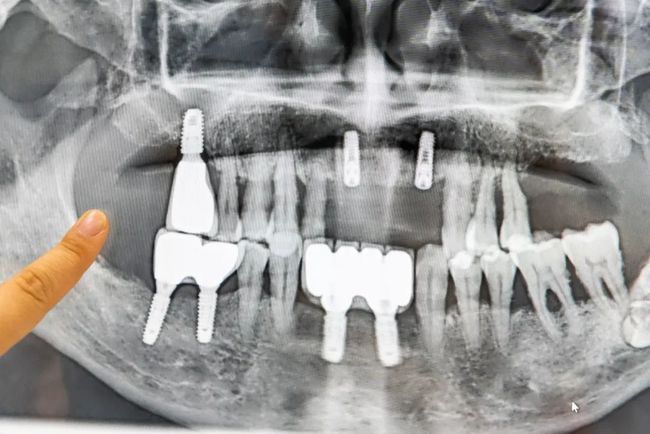

种植牙是口腔医学界公认的“理想修复方式”,被誉为“人类的第三副牙”。它对邻牙没有破坏性,无论是形态、色泽、牢固程度、咀嚼功能等,均堪比真牙。

医生还为我们介绍了种植的适用范围

单颗牙缺失、多颗牙缺失、

半口缺失、全口缺失等

种植牙不需要损伤两侧的邻牙,

不仅坚固耐用,还可以防止牙骨萎缩。

医生介绍,

如果自然牙的最大咀嚼力是100的话,

那么假牙的咀嚼力是15~20,

而人工种植牙能发挥到80~90的力度。